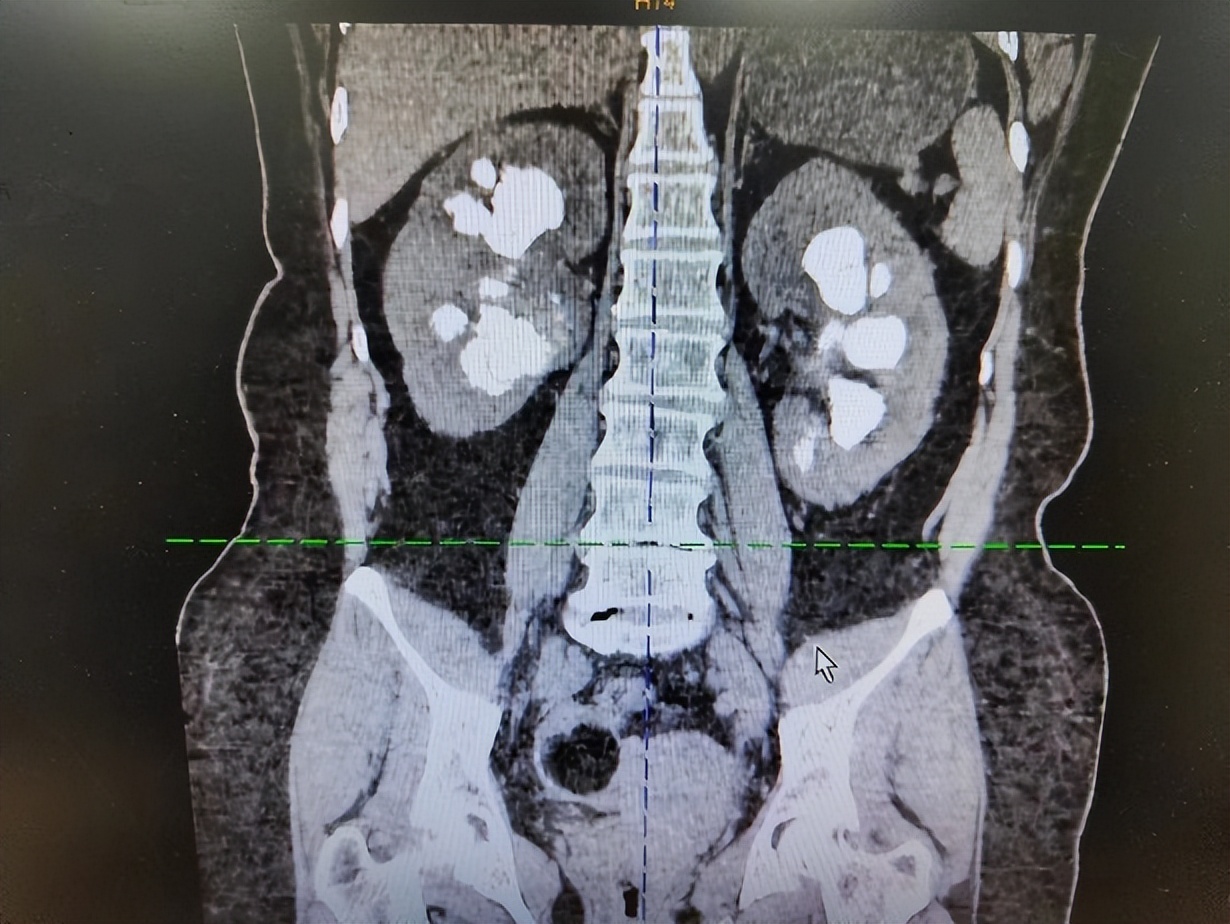

抱着赌一把的心态,患者及家属来找到了黄耀,完善CT等检查后发现,患者双肾柱形结石,两边均超过8cm,每个肾盏都塞满了结石。“我们团队经过讨论后,建议先进行一侧经皮肾镜碎石手术,但是患者结石太大太多,难以取尽,告知患者及家属后,他们虽有诸多疑虑,但还是同意了手术方案。”黄耀回忆道,这个手术采用的多通道模式,最后顺利完成了,将患者大部分结石清除。

但是术后,患者心态比较紧张,情绪也会偶尔失控。 随着病情的好转,反复与患者沟通交流,患者的心态也逐渐缓和下来,术后复查见数个肾盏仍有部分结石残留,但结石较分散,再行经皮肾镜碎石要取尽结石创伤较大,